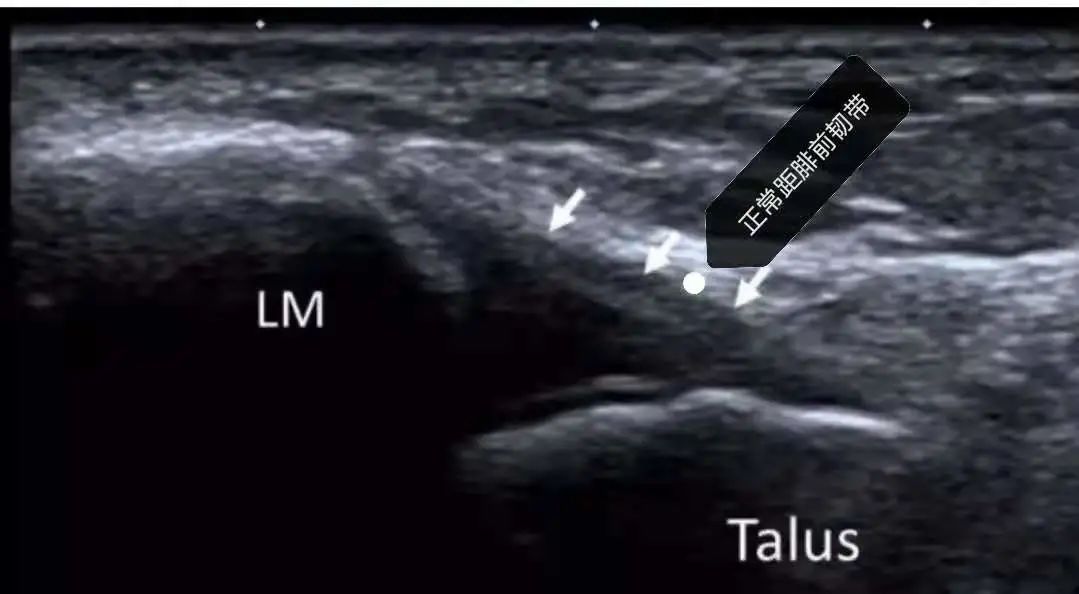

穿高跟鞋的小仙女崴了脚

正常分歧韧带及跟骨前上突

分歧韧带损伤伴跟骨撕脱骨折

打篮球脚崴了,拍个x片提供骨折情况,踝关节超声能提供距腓前韧带、跟腓韧带、分歧韧带以及肌腱是否连续,断端位置,积液情况!